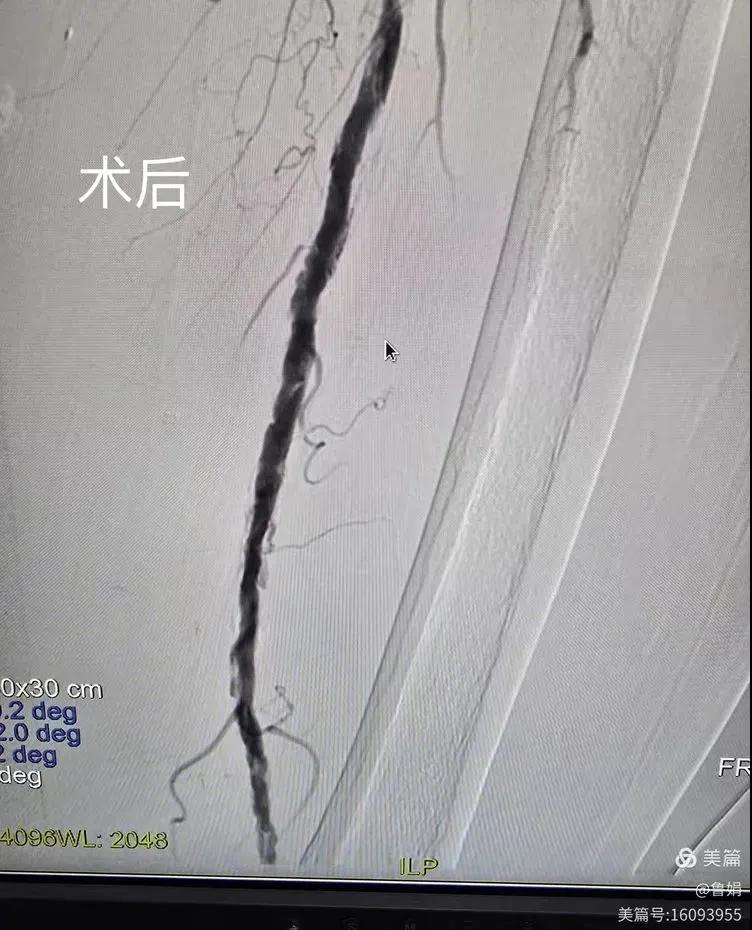

據(jù)悉,該患者,女,73歲,下肢動(dòng)脈硬化閉塞癥,“以靜息痛,間歇性跛行”入院,CTA評估:股淺動(dòng)脈,腘動(dòng)脈間斷性多段重度狹窄,外二科血管外科團(tuán)隊(duì)根據(jù)患者病情,結(jié)合檢查結(jié)果,經(jīng)過科室會(huì)診后,決定對該病人行介入治療。手術(shù)由周創(chuàng)業(yè)副主任與北大一院血管外科專家郭宏杰教授聯(lián)合開展,對股淺動(dòng)脈,腘動(dòng)脈重度閉塞段行血管開通+藥涂球囊擴(kuò)張成形,術(shù)后狹窄明顯緩解,血流恢復(fù)!

下肢動(dòng)脈閉塞的介入開通是外周介入領(lǐng)域難度最大的技術(shù)之一,這項(xiàng)微創(chuàng)介入手術(shù)的開展,實(shí)現(xiàn)了漯河市中醫(yī)院在下肢動(dòng)脈血管介入治療上零的突破,進(jìn)一步推動(dòng)了醫(yī)院介入治療技術(shù)的發(fā)展,讓患者足不出戶就能切實(shí)享受到優(yōu)質(zhì)的醫(yī)療資源,極大方便了患者就醫(yī)。(介入中心:魯娟)